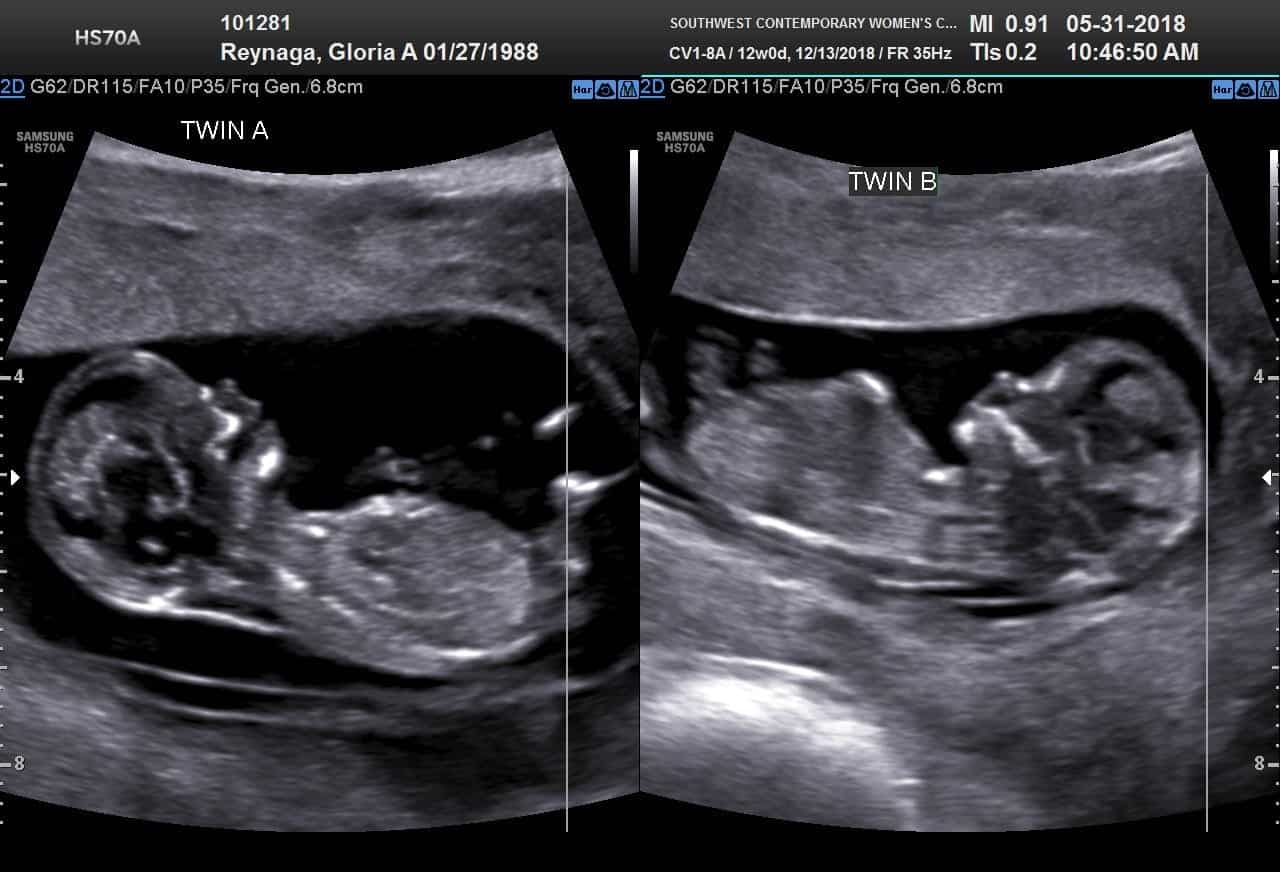

Ultrasound Photos at 12 Weeks Pregnant With Twins